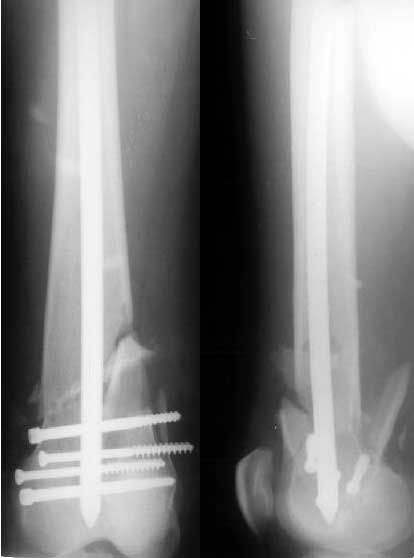

THX for the valuable suggestions about the subject. Actually we don't have a set for broken implant retrieval through the antegrade incision. So as we planned the piece was pushed out distally and the nail was replaced by the same but inserted from below. I locked it statically at the moment. Comments are welcome.

You said: " but inserted from below. I locked it staticallyat the moment."

I have a query. From the pictureit looks as if you used the usual proximal end as the distal end of nail. This means that you would have got the help of the zig to lock the distal end(near the knee). If this is correct how did you lock the holes near the trochanter?

DTIG> you would have got the help of the zig to lock the distal end (near the knee). If this is correct how did you lock the holes near the trochanter?

I didn't use the jig in the case. All screws were inserted using a self-made "radiolucent drill bit". I mentioned this before - tip of 2 mm wire is flattened to 3.5 mm and sharpened. It can be positioned over the hole using a plastic handle (see attached images). The one is made from a toy of my son :-) The technique works fine for me.